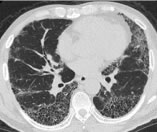

肺は肺胞という小さな風船状の袋がたくさん集まってできており、私たちはこの肺胞の壁を通じて酸素を取り込んでいます。間質性肺炎とは、この肺胞の壁に炎症や損傷が起こる病気の総称です。このような炎症や損傷は徐々に肺胞の壁を厚く硬くすると考えられています。病状が進行すると肺胞の壁が厚くなり酸素を取り込みづらくなります。また肺が硬くなることにより深呼吸がしづらくなります。肺胞の壁が硬くなることを線維化と呼び、一度線維化した部分は元の軟らかい肺に戻ることはありません。

間質性肺炎は原因によって以下のように分類されています。原因によって治療が異なることがあるため、問診、身体診察、血液検査、胸部CT、内視鏡検査や組織検査などの検査を行って原因の検討をします。肺の組織検査が正確な診断に必要なことが多いですが、組織検査には危険も伴うため、施行の是非は慎重に相談します。